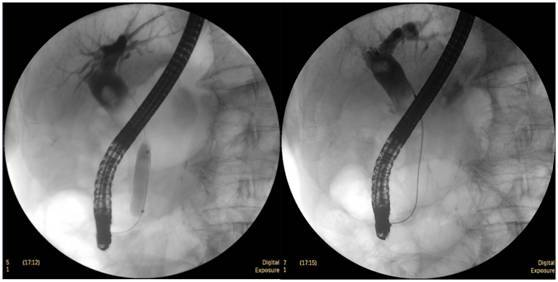

食管惡性腫瘤

食管癌并狹窄內(nèi)鏡下擴張支架植入術(shù),支架在脊柱背景下依然能清晰顯示。